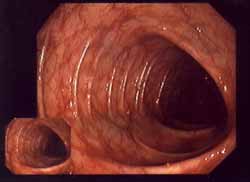

<A. 3.

Daño a la substancia genética (ADN) [por el mercurio de amalgama]

El

ácido desoxiribonucleico (ADN), esquema. El

DNS contiene grupos de nitrógeno que tienen

reacciones con el mercurio, y por eso la

substancia genética sufre un daño. La

"medicina convencional" no quiere

ver eso, y los gobiernos criminales y

calientes de la bolsa no bloquean el amalgama

hasta hoy... El ácido desoxiribonucleico (ADN), esquema. El DNS contiene grupos de nitrógeno que tienen reacciones con el mercurio, y por eso la substancia genética sufre un daño. La "medicina convencional" no quiere ver eso, y los gobiernos criminales y calientes de la bolsa no bloquean el amalgama hasta hoy...

Los elementos de la substancia genética (ADN = ácido desoxirribonucleico) contiene toda la información de la construcción del cuerpo y del metabolismo. Eso ADN contiene grupos de nitrógeno (N) que pueden reaccionar con el mercurio.

Las "letras" del ADN (incl. ADN mitocondrial) son cinco bases diversas. El mercurio se liga sobre todo al las bases timidina y uracilo, menos a adenosina, guanina o citosina. Por la formación de más radicales van ser provocados daños en la información genética, y eso puede provocar

-- cáncer

--  o la muerte celular.> (p.37)